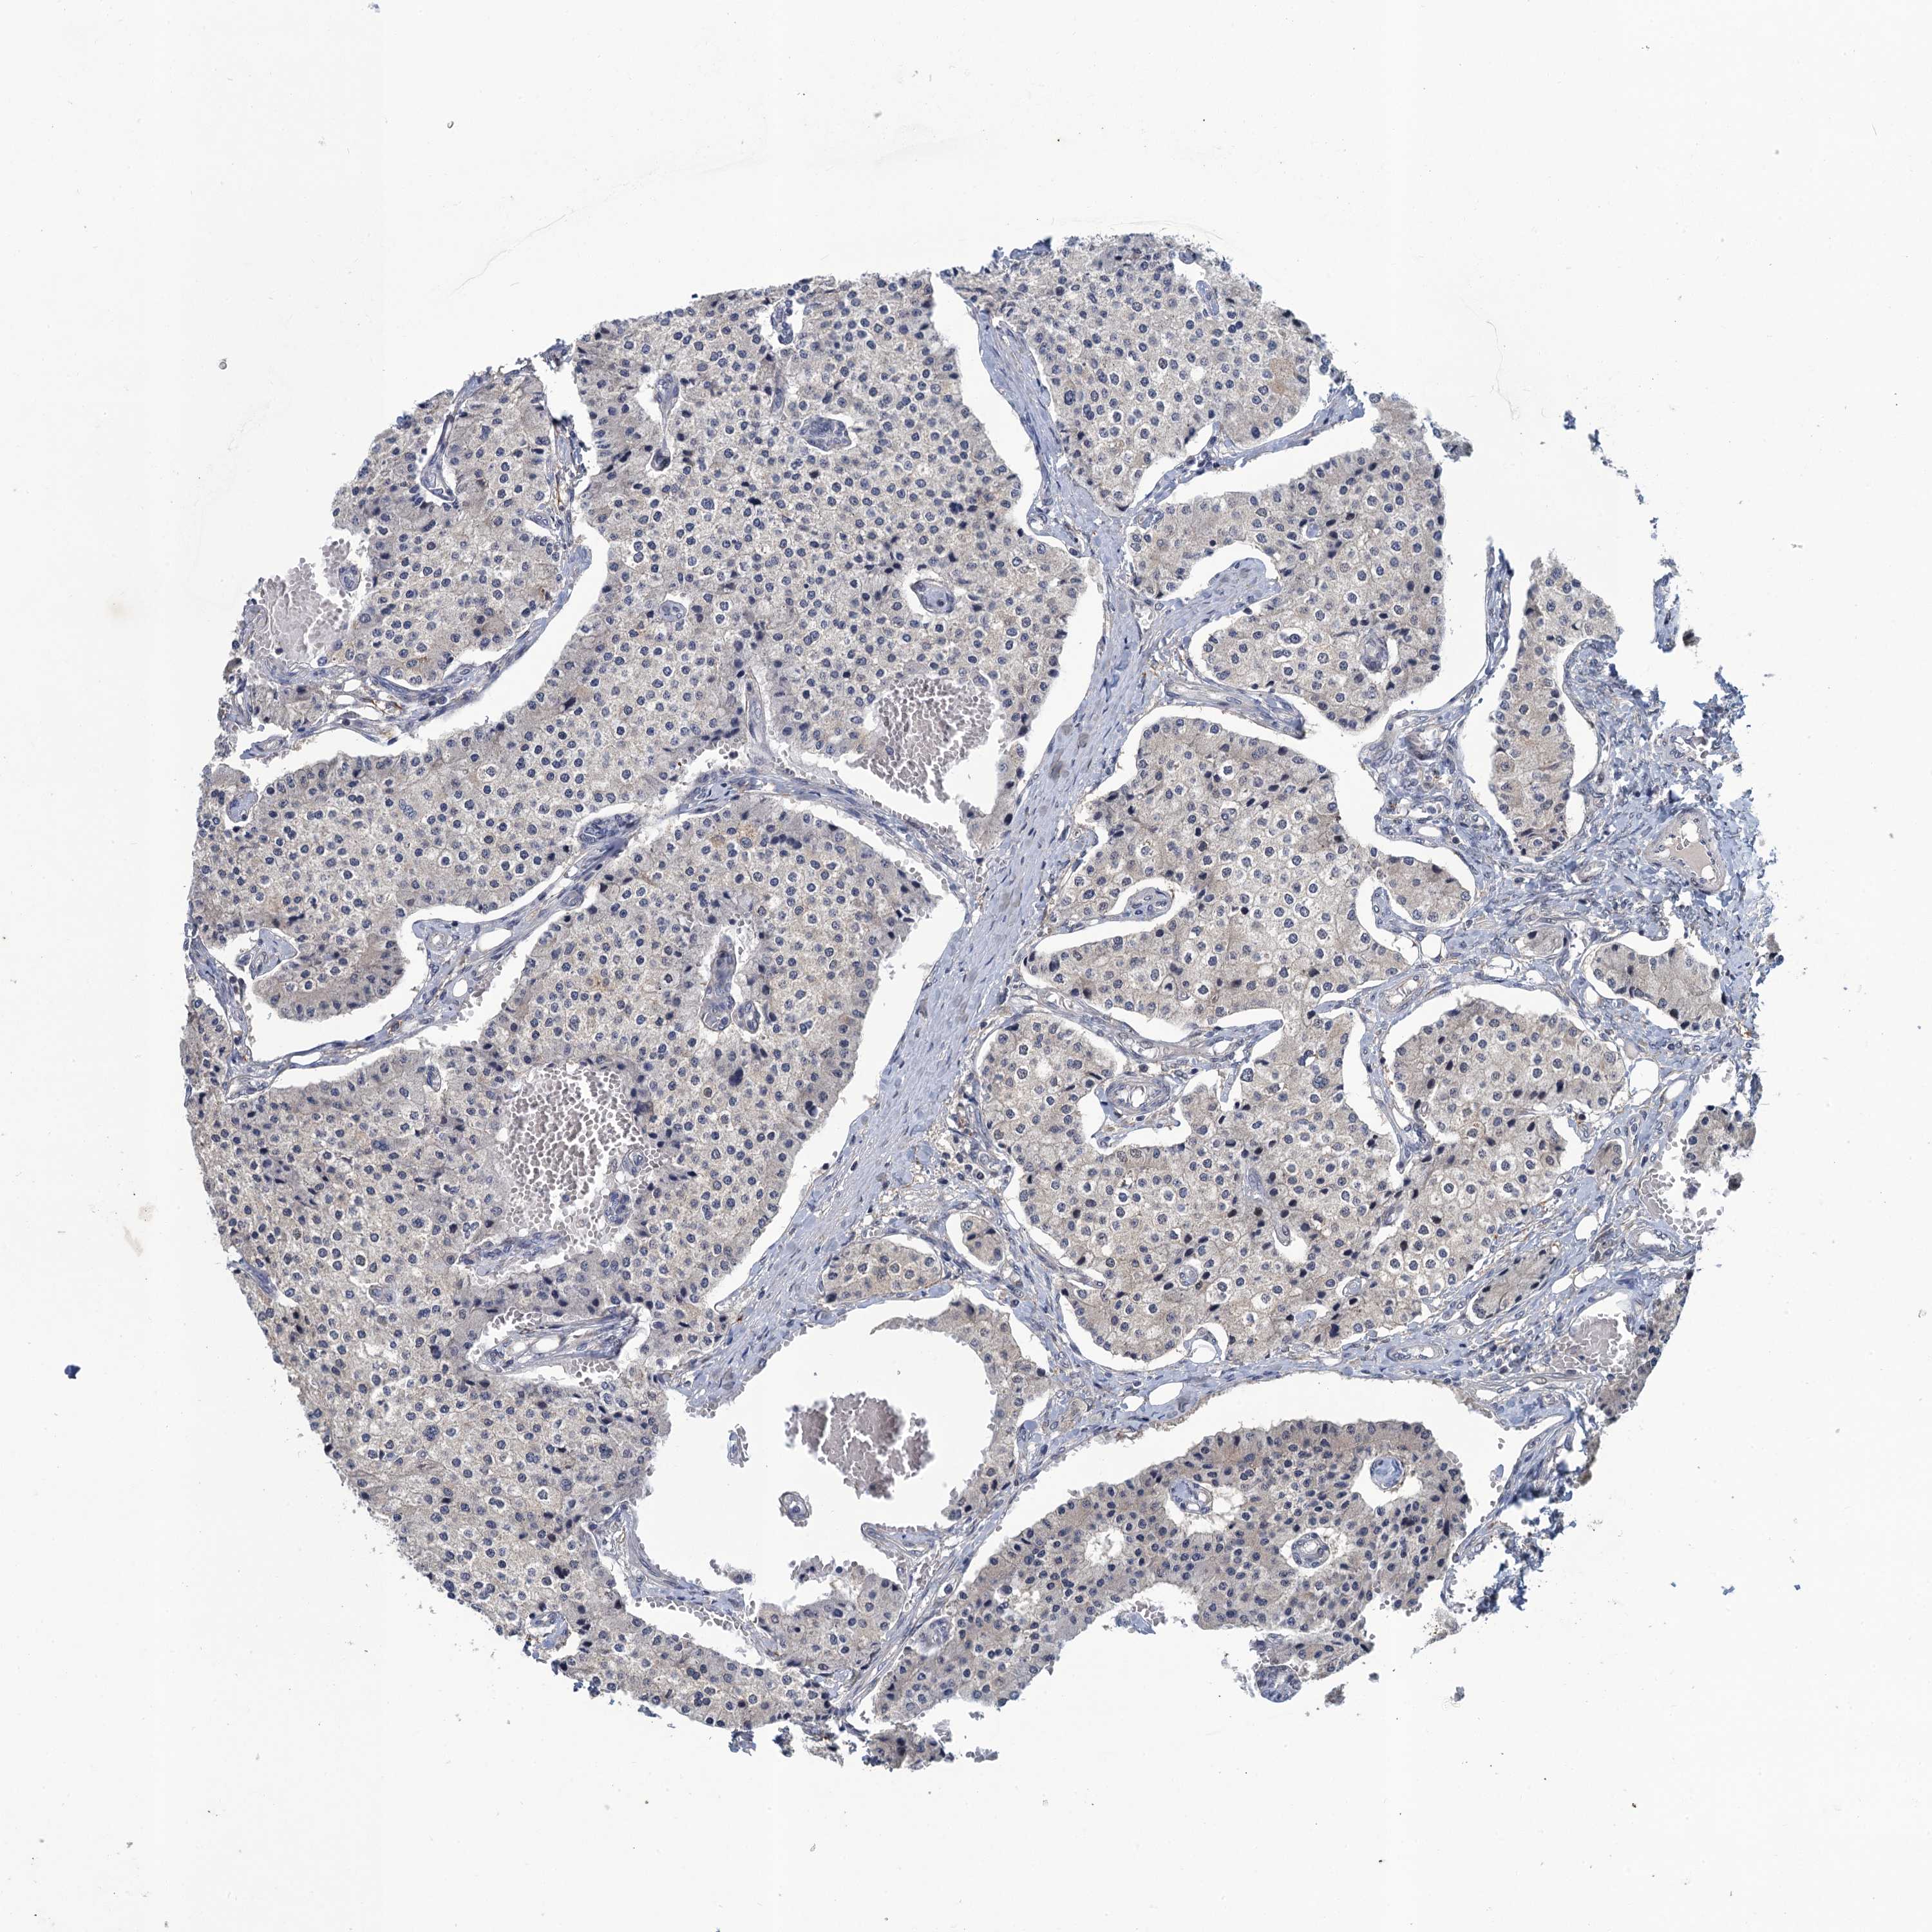

CARCINOID - Protein expressioni

A mouse-over function shows sample information and annotation data. Click on an image to view it in a full screen mode. Samples can be filtered based on level of antibody staining by selecting one or several of the following categories: high, medium, low and not detected. The assay and annotation is described here.

Note that samples used for immunohistochemistry by the Human Protein Atlas do not correspond to samples in the TCGA dataset.

Antibody stainingi

Antibody staining in the annotated cell types in the current human tissue is reported as not detected, low, medium, or high, based on conventional immunohistochemistry profiling in selected tissues. This score is based on the combination of the staining intensity and fraction of stained cells.

Each image is clickable and will lead to virtual microscopy that enables deeper exploration of all samples and also displays staining intensity scores, fraction scores and subcellular localization as well as patient and tissue information for each sample.

Antibody CAB042447

Staining

High

Medium

Low

Not detected

Intensity

Strong

Moderate

Weak

Negative

Quantity

>75%

75%-25%

<25%

None

Location

Nuclear

Cytoplasmic/membranous

Cytoplasmic/membranous,nuclear

Carcinoid, malignant, NOS

Carcinoma, NOS